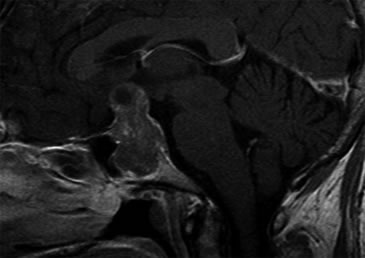

Se realizó una campimetría que evidenció una hemianopsia heterónima temporal. Una RM (Resonancia Magnética) posterior confirmó el hallazgo de adenoma hipofisario de 42 x 34 x 25 mm que realzaba moderadamente con en el contraste paramagnético, con varios quistes de retención glandular (el mayor de aproximadamente 1 cm de diámetro), con extensión supraselar e invasión del seno esfenoidal y seno cavernoso derecho con desplazamiento y compresión del quiasma óptico y del tallo hipofisario (Figuras 1 y 2).

Figura 1. Corte sagital en secuencia T1 con gadolinio.